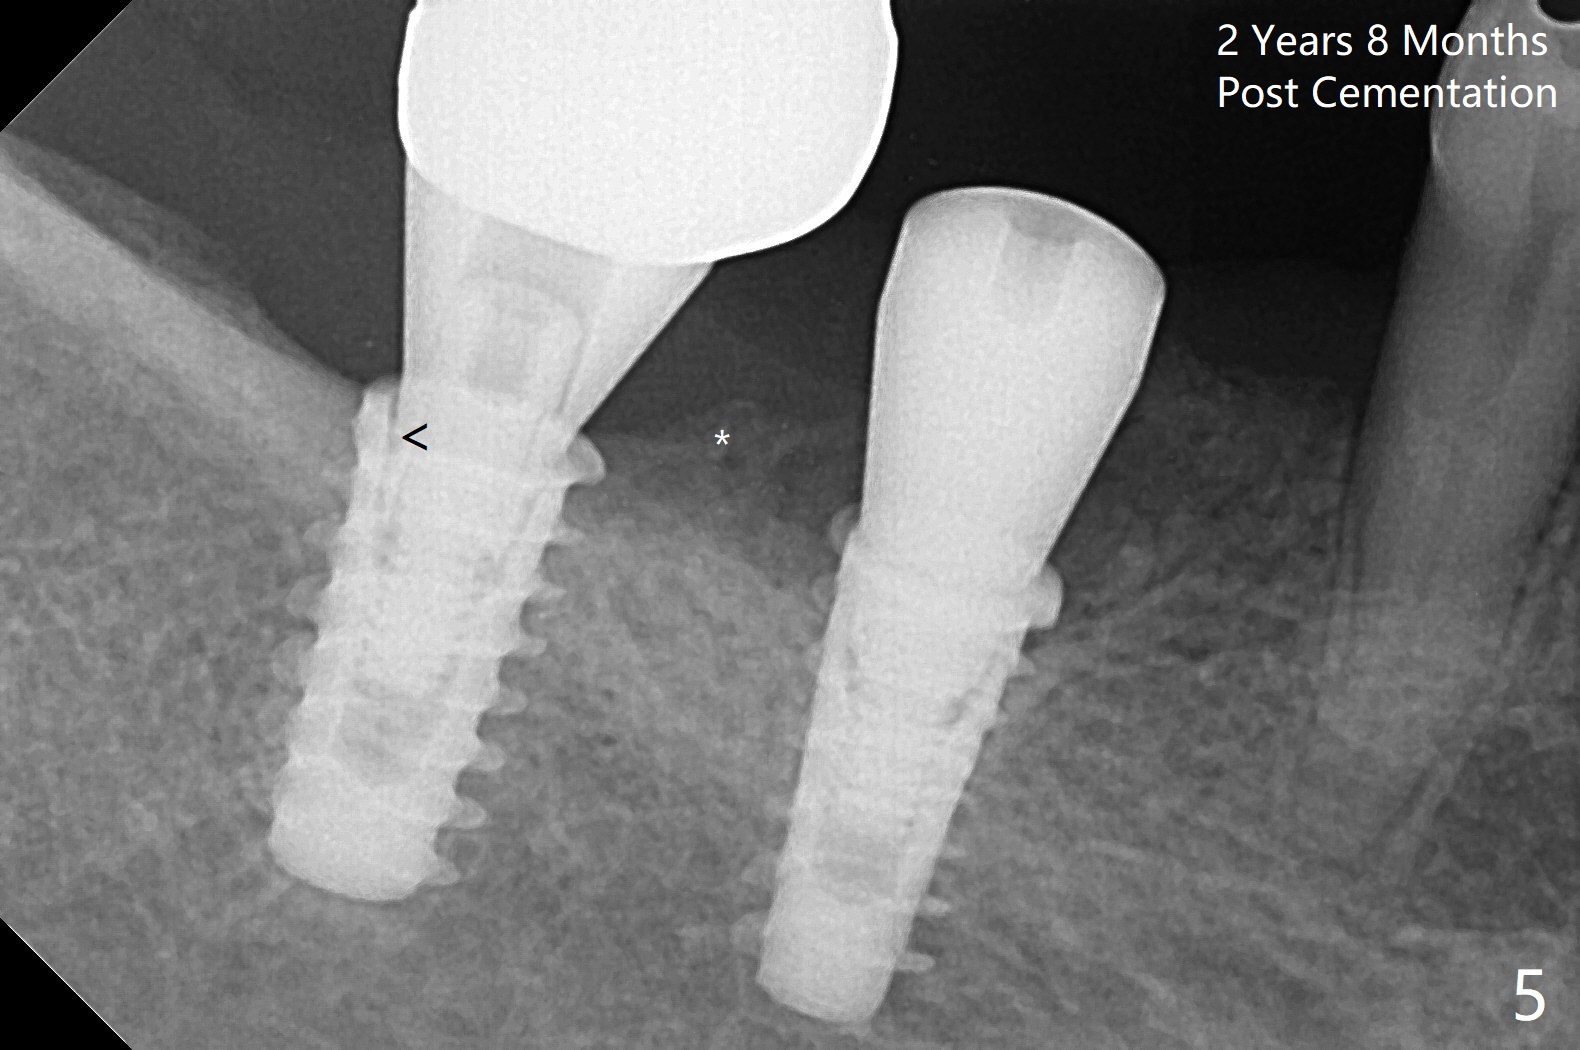

Following osteotomy, 4.5x11 and 5x9 mm dummy implants are placed at the sites of #30 and 31, respectively (Fig.1).  Due to limited inventory of Magicore and patient's in-cooperation, FC implants (4.5x9 and 5x9 mm) are placed (Fig.2).  A healing abutment (6x4 mm) is placed at #31 because of low torque (overprep), while a pair abutment (6.5x5.7(4) mm) is placed at #30.  Vera Graft is placed with autogenous bone (*).  The implant/abutment ratio at #30 is unfavorable.  If the implant turns out to be loose, immediate implant should be larger in the future.  Note bone growth, especially at #30, 2.5 and 4 months postop (Fig.3,4).  In fact the abutments are incompletely seated.  The crown of #30 is loose 2 years 8 months post cementation, while the abutment at #31 remains incompletely seated (Fig.5).  The latter is completely reseated after separating the crown, while a smaller one is seated at #30 (Fig.6) due to use of a small healing abutment earlier (Fig.5).  A good piece of news is the presence of the bone between the implants (Fig.5,6 *), which contributes to interimplant papilla.  Return to Lower Molar Immediate Implant, Prevent Molar Periimplantitis (Protocols, Table), IBS77, 2-5 Xin Wei, DDS, PhD, MS 1st edition 09/22/2017, last revision 12/01/2020